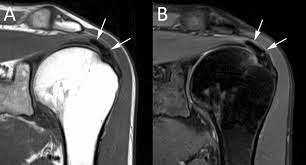

MRI (Khi cần)

• Đánh giá mức độ tổn thương gân

• Phân loại Loew (MR morphology)

• Loại trừ rách gân bộ phận/hoàn toàn

• Chỉ định trước phẫu thuật

🖼 Hình 6 – MRI coronal gân trên gai: vôi hóa & tổn thương gân

Fat-suppressed T2 coronal: ổ tín hiệu thấp trong supraspinatus, dấu hiệu bursitis

MRI coronal gân trên gai vôi hóa